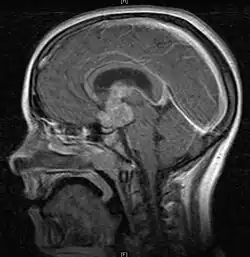

• Mainly located in midline structures, suprasellar region or pineal gland, also basal ganglia and hypothalamus

• Natural spread believed to be along subependymal lining of 3rd and 4th ventricles, leading to intraventricular relapse before spinal dissemination

Location